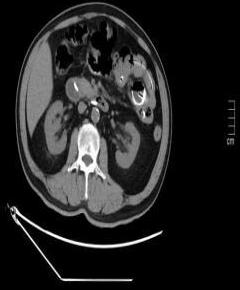

• 单侧双通道内镜下椎间盘切除术治疗钙化型腰椎间盘突出症的临床疗效分析

摘要:目的 观察单侧双通道内镜(UBE)下椎间盘切除术治疗钙化型腰椎间盘突出症(CLDH)的临床疗效。方法 回顾性分析2020年1月-2022年1月在该院行UBE下腰椎间盘切除术的25例单节段CLDH患者的临床资料。记录手术时间、术后住院时间和术后并发症情况。采用腰腿痛视觉模拟评分法(VAS)评分、腰椎日本骨科协会(JOA)评分和Oswestry功能障碍指数(ODI),评估术前、术后3 d、术后1个月和末次随访的临床疗效。末次随访时,采用改良Macnab标准,评估优良率。结果 术后随访12~24个月,平均(15.60±2.60)个月。手术时间为(58.67±10.73)min,术后住院时间为(4.65±0.63)d。术后3 d、术后1个月和末次随访时的VAS评分和ODI明显低于术前,JOA评分明显高于术前,差异均有统计学意义(P < 0.05)。末次随访时,根据改良的Macnab标准,15例为优,9例为良,1例为可,优良率为96.00%(24/25)。术后并发症:1例神经根腹侧硬膜囊撕裂,长度约5 mm,未行硬膜囊修补术,术后嘱患者卧床5 d,给予补液治疗,患者下床活动未诉头痛等不适,术后MRI显示:未见硬膜外大量积液;1例出现下肢感觉障碍,给予营养神经药物对症治疗,术后1个月随访时恢复。术后影像学检查显示:游离钙化组织基本被完全切除,神经根得到充分减压。末次随访时,未发现复发病例。结论 UBE下腰椎间盘切除术治疗CLDH安全、有效,值得应用于临床。